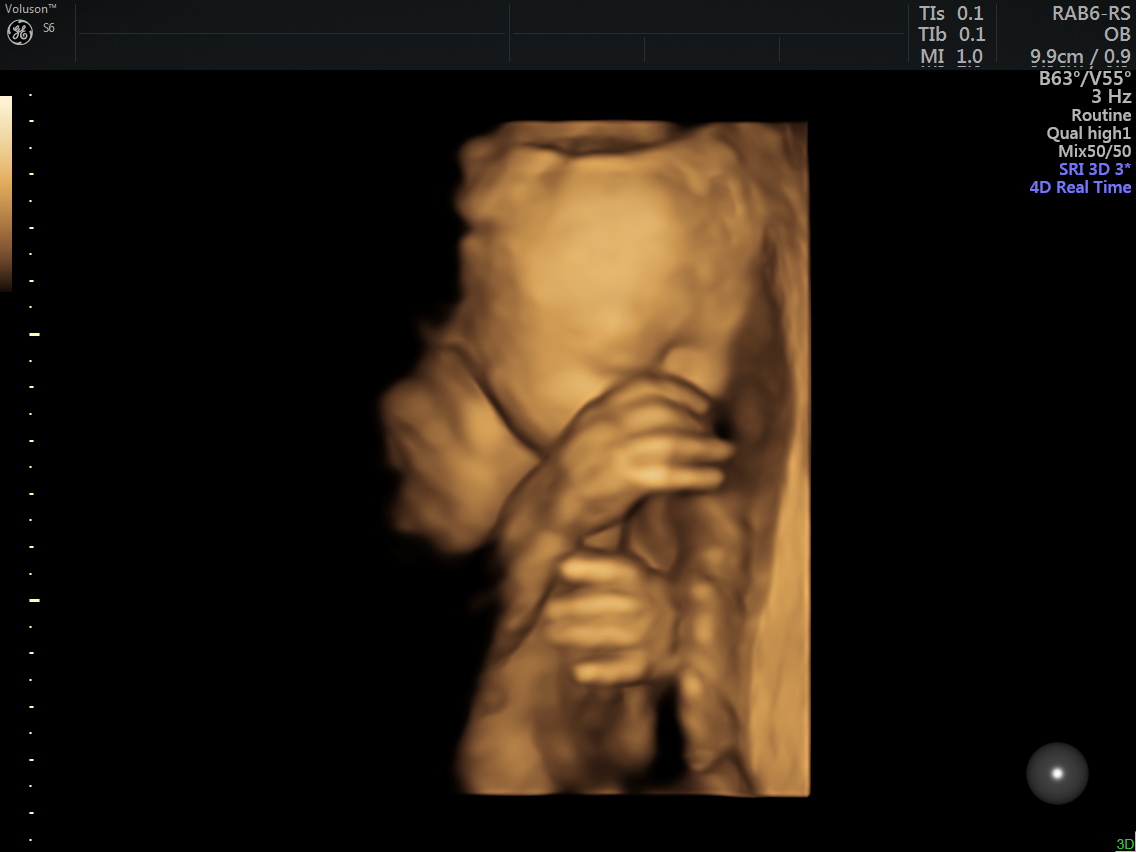

4 Boyutlu Renkli Ultrason

4D (dört boyutlu), Renkli, Ayrıntılı Gebelik Ultrasonu

Anne adayı 4D Renkli Ultrason Sayesinde Bebeğine Daha Kolay Bağlanabilir.

4 boyutlu renkli ultrason cihazı ile çok erken dönemde cinsiyet, yarık dudak, yarık damak, eksik parmak, beyin ve omurilikten kaynaklanan rahatsızlıkların erken tanısı konulabiliyor.